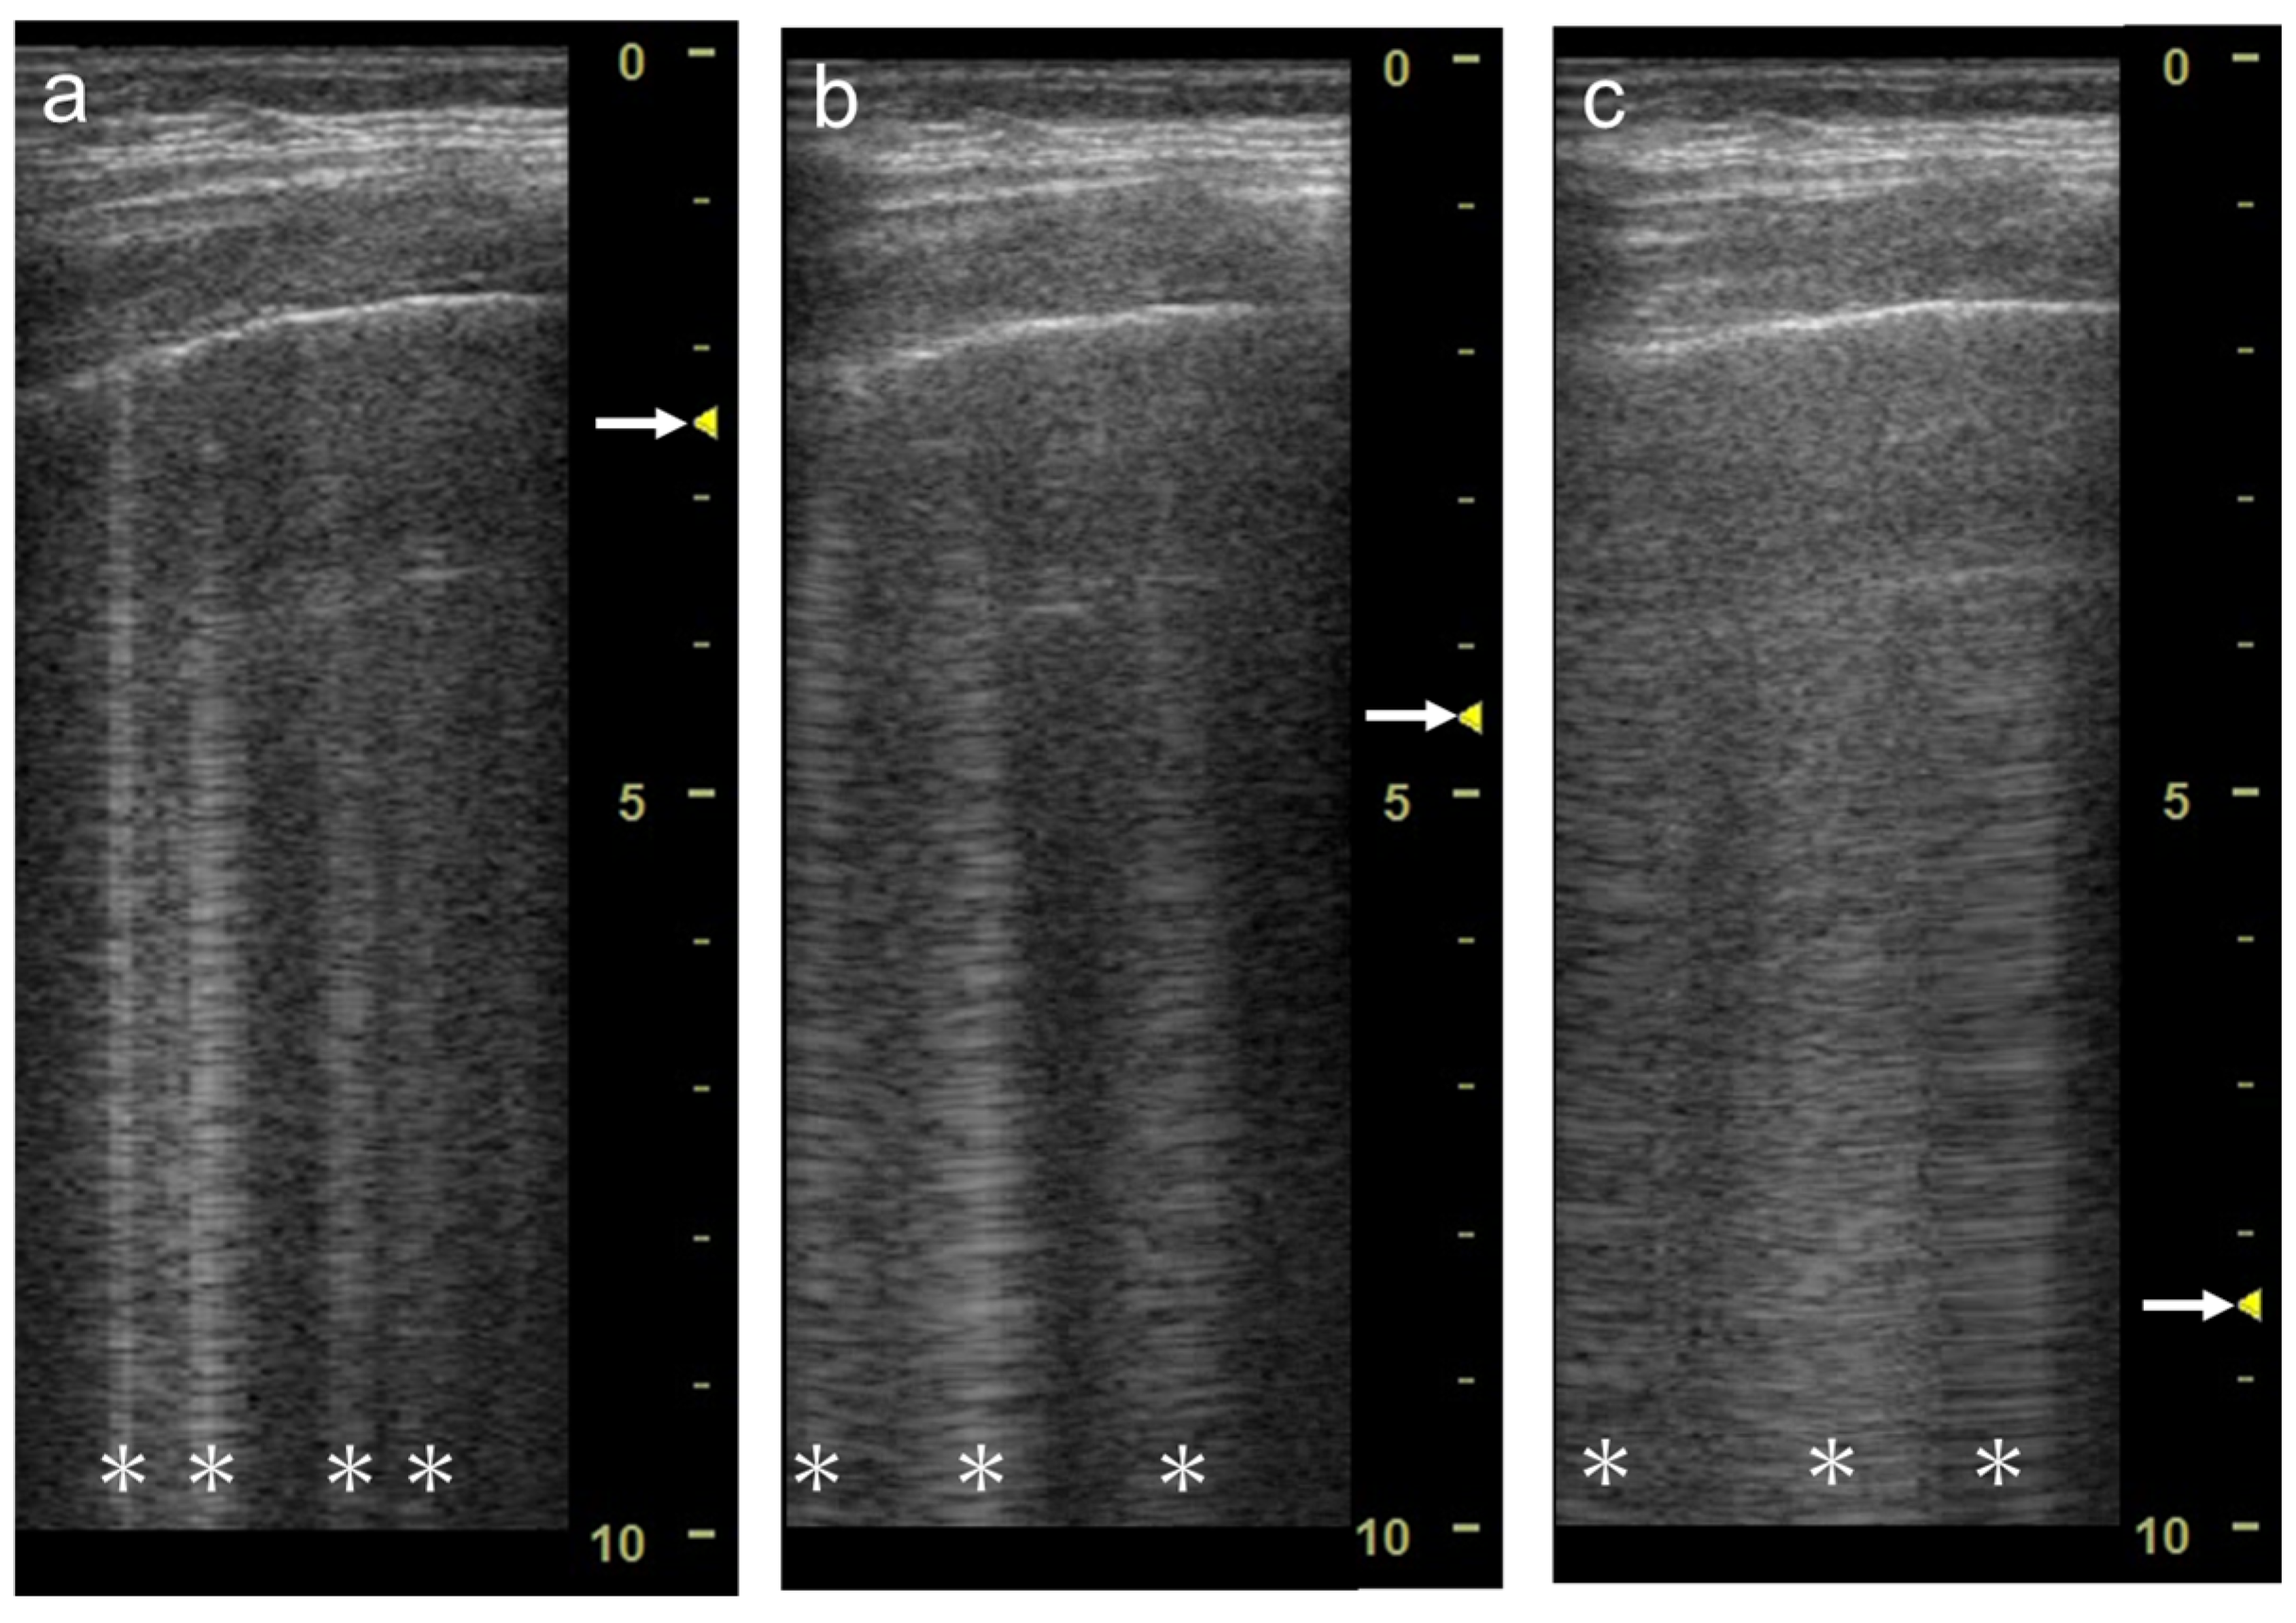

3.1. Spatial Compound Imaging

3.2. Focal Point

3.3. Frequency

3.4. Selection of Transducers